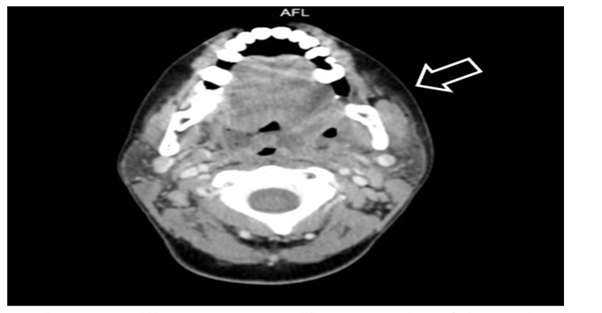

Our ENT clinic at Saudi German Hospital received a patient who had endured a record number of acute tonsillitis attacks. We examined this 40-year-old female and found red swollen tonsils. The diagnosis confirmed that she was suffering from chronic tonsillitis. Preoperative examinations including laboratory investigations and electrocardiography were normal; therefore, the patient was admitted and a tonsillectomy was performed under general anesthesia, which was induced by protocol and maintained by sevoflurane. Monopolar electrocautery dissection was used to remove the tonsils and hemostasis was attained through bipolar cautery. The operation was uneventful, and the patient recovered promptly from anesthesia, without vigorous coughing or violent neck movement; however, she began to complain of left painful submandibular swelling six hours following the operation. A marked crepitus was detected and a visible pulsation was seen on oral examination; this conformed surgical emphysema, which extended from the mandibular angle to the left side of the upper area of the neck. The patient was regularly monitored and her condition was found to be good, with minimal signs of airway compromise in the first 24 hours which then improved gradually. Computed tomography angiography of the neck was performed (Figure 1) and a small collection of serous fluid was discovered on the left operative bed, as well as marked surgical emphysema on the left side of the neck that reached superiorly to the skull base level and inferiorly to the upper mediastinum. The chest radiograph results were normal without any indication of pneumomediastinum or pneumothorax. Immediately subsequent to this diagnosis, a pressure dressing, high flow oxygen and further intravenous antibiotics were administered to the patient including Augmentin and Flagyl, steroid was not given. The patient showed significant improvement and exhibited a noticeable reduction in swelling after four days. Furthermore, to assess the pharyngeal wall, a gastrografin swallow was performed, which showed no fistulous tracts or contrast leakage. A follow-up computed tomography of the neck (Figure 2) indicated a significant reduction in the volumes of the previously observed fluid and air locules. The patient was monitored at the hospital for an additional four days, and then discharged in a generally good condition.

Figure 1 Computed tomography of the neck reveals subcutaneous emphysema. The arrow indicates the presence of air in the left side of the neck.